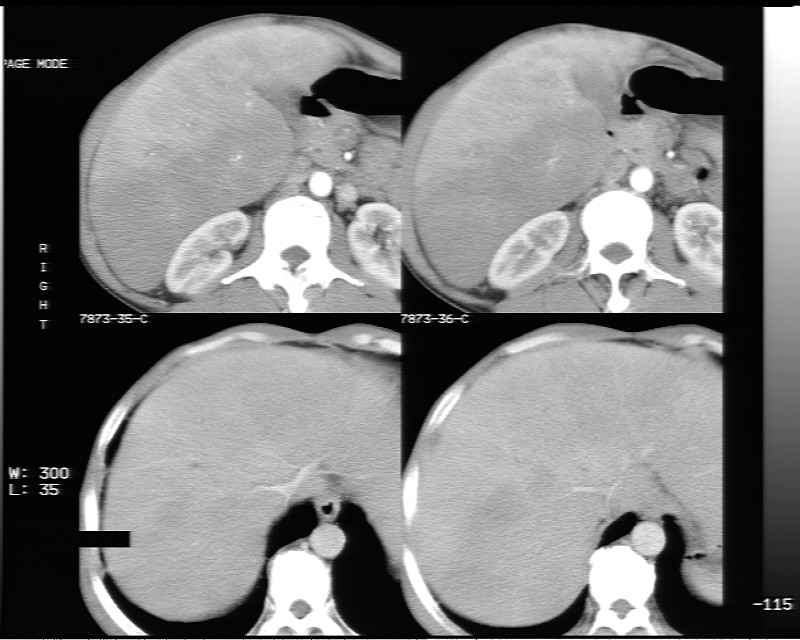

动态增强示:

支持脂肪肝【无占位性,高低密度区同期强化,平扫与强化的密度成比例】

1.脂肪肝;

2.右肾结石。

不均匀性脂肪肝 。支持!右肾结石

1、不均匀脂肪肝;2、布加氏综合症(肝脏肿大,门脉纤细,下腔海绵状变性,肠系膜上静脉显著扩张)。